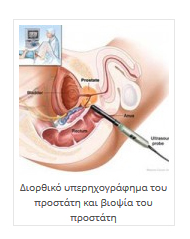

Εξωτερική Ακτινοθεραπεία με Γραμμικό Επιταχυντή

Εξωτερική Ακτινοθεραπεία με Γραμμικό Επιταχυντή- Σύμμορφη τρισδιάστατη ακτινοθεραπεία (3D Conformal)

Η κατανομή δόσεως ακτινοβολίας κατά την κλασσική εξωτερική ακτινοθεραπεία. Η μικρότερη του ενός χιλιοστού (< 1 mm) απόκλιση της ευστοχίας κατά την ακτινοβόληση με CyberKnife®, προφυλάσσει τις γειτονικές δομές (όπως το ορθό και την ουροδόχο κύστη) και αυτό σε συνδυασμό με τη δυνατότητα υποκλασματοποίησης (λίγες συνεδρίες – επισκέψεις αλλά αυξημένης εντάσεως – δόσεως κάθε φορά) επιτρέπει ραδιοβιολογικά πολύ ισχυρή δόση ακτινοβολίας στον κακοήθη ιστό χωρίς τις επιπλοκές που παρατηρούνται όταν τα όρια της ακτινοβόλησης ξεφεύγουν προς τους γειτνιάζοντες ιστούς.

Ισοδοσικές καμπύλες από πλάνα θεραπείας του προστάτη που δείχνουν πόσο ελάχιστη δόση ακτινοβολίας βγαίνει εκτός του προστάτη με θεραπεία CyberKnife.